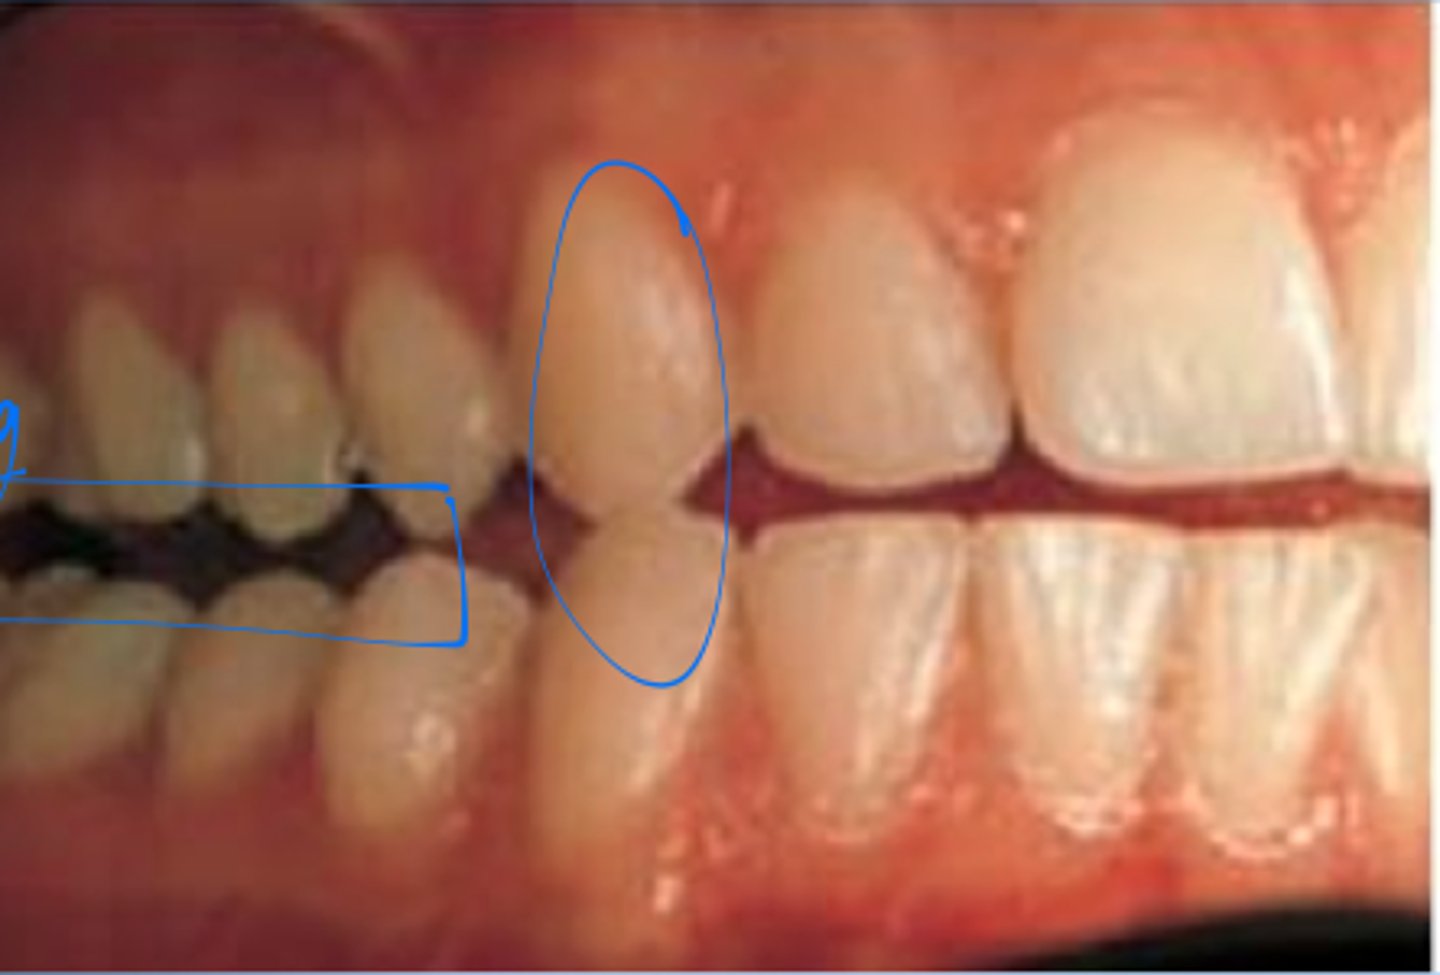

<p>what class of occlusion is this?</p>

what class of occlusion is this?

class II